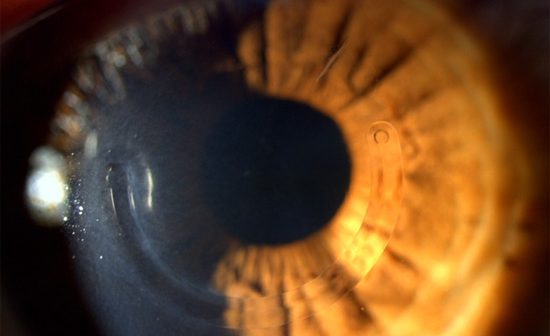

La fréquence du kératocône est difficile à évaluer en raison de l’absence de critères diagnostiques précis. Elle dépend de la prise en compte des formes frustes ou suspectes. L’incidence du kératocône est estimée à 1/2 000 [1].

L’âge de survenue du kératocône varie selon les séries. Une série multicentrique de 38 centres portant sur 1 579 patients rapporte un âge moyen de découverte de 27,3 ± 9,5 ans avec près de 90 % des patients diagnostiqués entre 10 et 39 ans (tableau I) [2]. L’âge de découverte pouvant être très différent de l’âge de survenue de la maladie, un enfant d’un parent atteint de kératocône devra bénéficier d’un dépistage topographique dans sa deuxième décennie de vie. Ce dépistage peut se situer aux alentours de la puberté, période fréquemment associée au début de la maladie sans qu’aucun facteur hormonal n’ait pu clairement être mis en évidence.

La découverte d’un kératocône chez un enfant, soit avant 15 ans, imposera un traitement systématique rapide par cross-linking du collagène cornéen. La rapidité d’aggravation dans ce contexte dispense d’une surveillance pour documenter la progression du kératocône. En dehors de “kératocônes pédiatriques”, le cross-linking du collagène cornéen s’effectue en cas de progression avérée. Cette progression est variable. Amsler, en 1946, sur une série portant sur 286 yeux avec un suivi de 3 à 8 ans, rapporte une aggravation dans 22 % des yeux [3]. La progression était maximale entre 10 et 20 ans, ralentissait entre 20 et 30 ans et rare après 30 ans.

Plus récemment, la progression a été rapportée sur une série multicentrique de 1 032 patients avec un profil proche de celui rapporté par Amsler (tableau II) [4]. L’absence de progression dans un certain nombre de cas, dans toutes les catégories d’âge, hors enfants, incite à ne pas traiter systématiquement par cross-linking. La surveillance, au mieux semestrielle au moment de la découverte du kératocône, souvent entre 20 et 30 ans, pourra ensuite être élargie si une stabilité est retrouvée sur 2 à 3 examens successifs, ou après 30 ans. Même si la progression ralentit entre 30 et 40 ans, les patients doivent être prévenus du risque d’aggravation imprévisible, même tardif, et de la nécessité de continuer une surveillance.